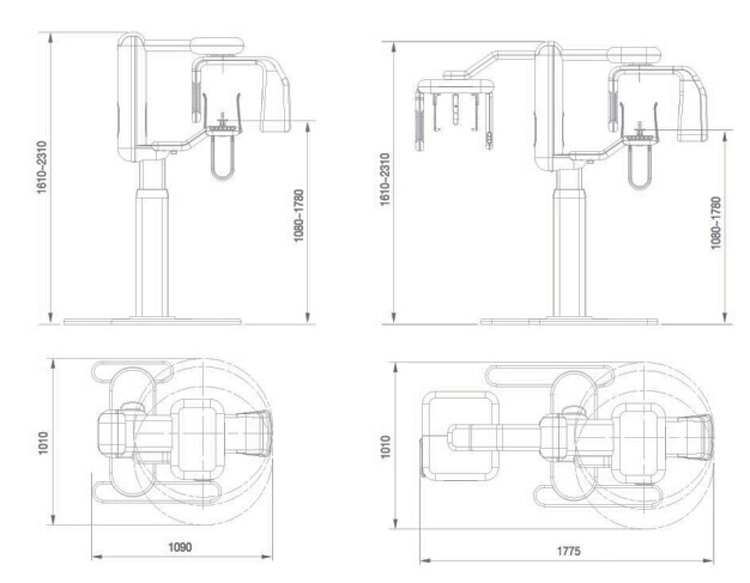

MY-D068A radiology equipment medical digital panoramic dental x ray machine

MY-D068A- Description

Specifications